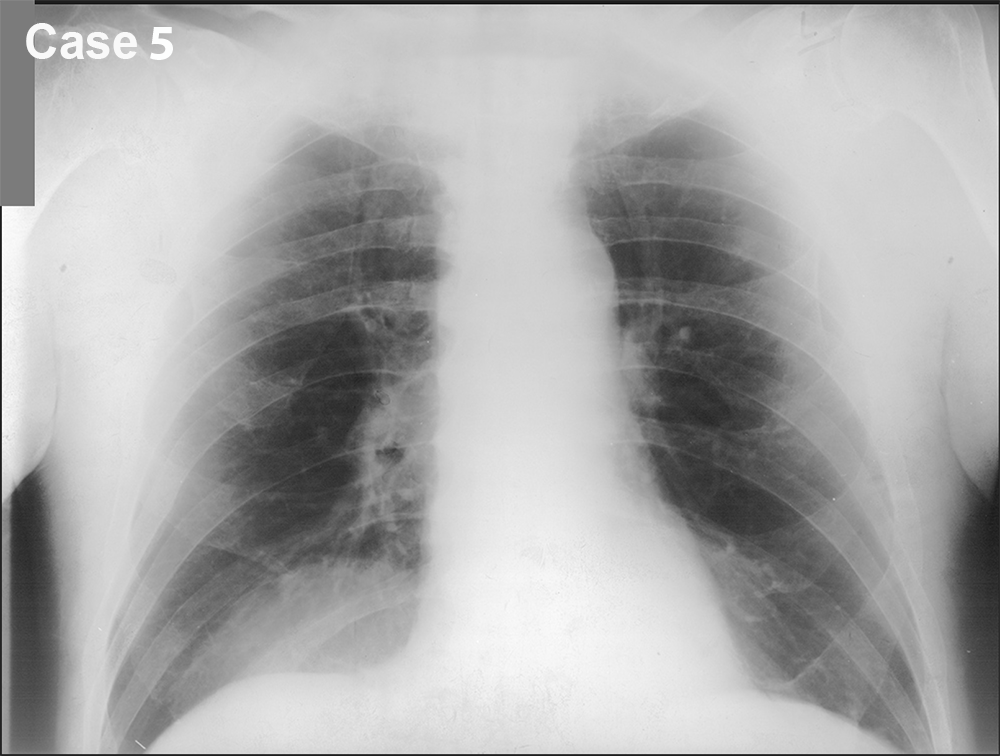

You are given a review of the ABCDE approach to frontal CXR interpretation and five cases to preview before class.

For each of these five cases, try to identify what is most abnormal, using the ABCDE framework to organize your search. Be descriptive! Try not to jump to conclusions regarding the final diagnosis. We will discuss each case in more detail in class. You can also consider what the next imaging study should be, and can make use of the ACR Appropriateness Criteria to help in this decision. You can also search the STR website for educational materials pertinent to each case.